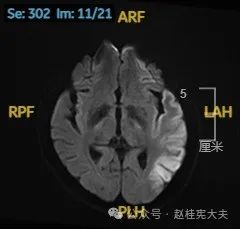

入院后给予精氨酸,左卡尼丁,辅酶Q10,维生素E等治疗。患者病情稳定好转中,2天后意识清楚,语言表达仍欠佳。当天复查颅脑磁共振如下:

以上为患者发病后3次的颅脑磁共振片子,临床诊断基本上可以确认了,希望患者逐渐恢复!